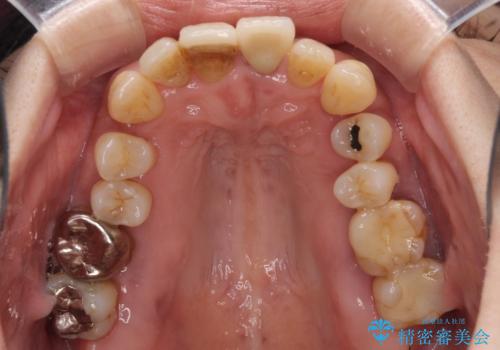

歯周病でグラグラの歯 矯正治療と歯周外科を併用した総合歯科治療

- 近医に通い続けるも、一向に不快感が改善しないとのことで来院された患者様です。

診察を行ったところ、重度歯周病の状態の上に上下の歯列が著しい叢生という状態でした。

歯周初期治療として抜歯や歯槽骨再生治療を行い、さらに歯周ポケット除去を行った後に矯正治療で歯列を整えて行くこととしました。